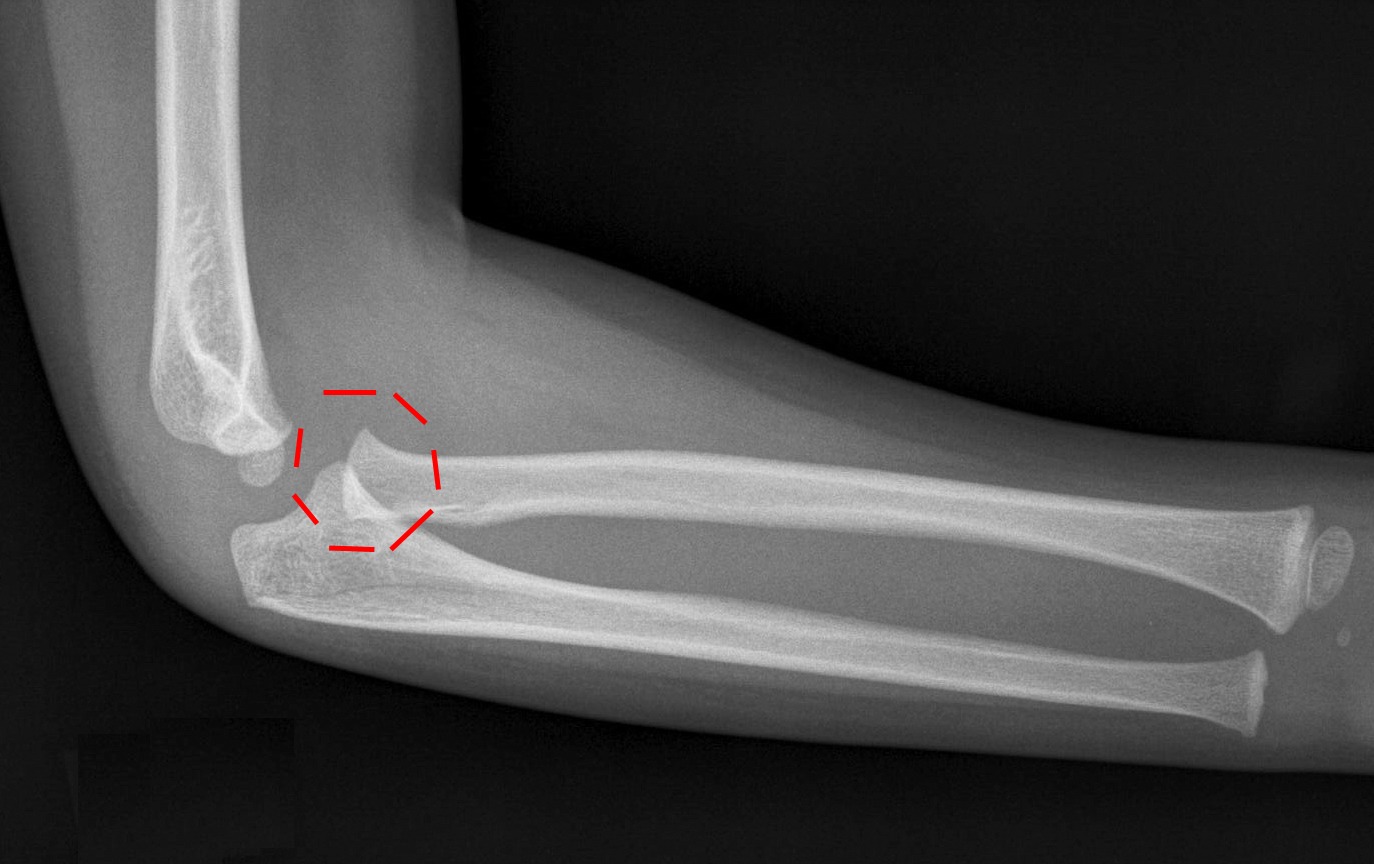

Elbow XRays

ELBOW DISLOCATION WITH RADIAL HEAD FRACTURE Radius Dislocation Elbow Terrible triad injury of elbow is a traumatic injury pattern of the elbow characterized by elbow dislocation, radial head/neck fracture, and a coronoid. The humerus (your upper arm bone). The ulna (the longer bone in your. Elbow dislocations account for 10% to 25% of elbow injuries, most common. Your elbow joint is where three bones in your arm come together:. Radius Dislocation Elbow.

Elbow XRays Radius Dislocation Elbow A person with a radial head subluxation has a partial dislocation, where the annular ligament that holds the radial bone in. Terrible triad injury of elbow is a traumatic injury pattern of the elbow characterized by elbow dislocation, radial head/neck fracture, and a coronoid. Your elbow joint is where three bones in your arm come together: Elbow dislocations are common. Radius Dislocation Elbow.